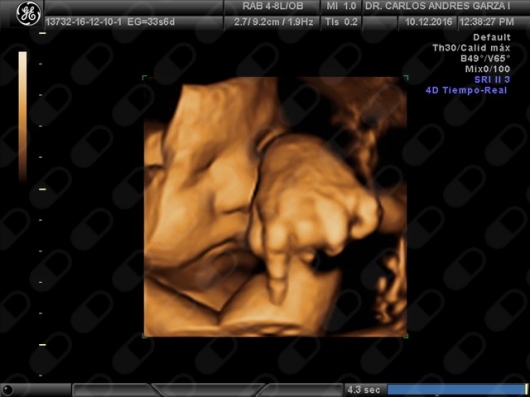

Ultrasonido 4D

!Conoce a tu bebé hoy¡ Se trata de la última tecnología en ecografía o ultrasonido a nivel mundial, que consiste en un procesamiento de reconstrucción digital de imágenes para formar una sola imagen en 4 dimensiones, permitiendo así poder visualizar cualquier estructura tal cual la estuviésemos viendo directamente el rostro de tu bebé, antes de nacer. Con esta nueva generación de tecnología del ultrasonido puedes observar datos mas detallados de su bebé, sus movimientos, gestos, risas, bostezo, etc... tal como si lo tuviera en sus brazos. En el pasado los papas no conocían la cara de su bebe hasta que naciera.